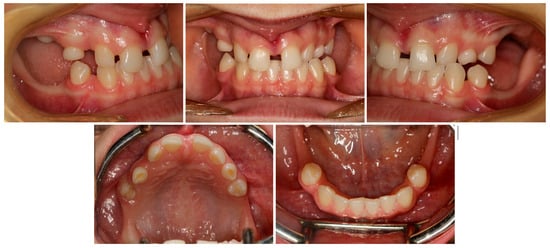

2. Materials and Methods

3. Results

3.1. Treatment Process